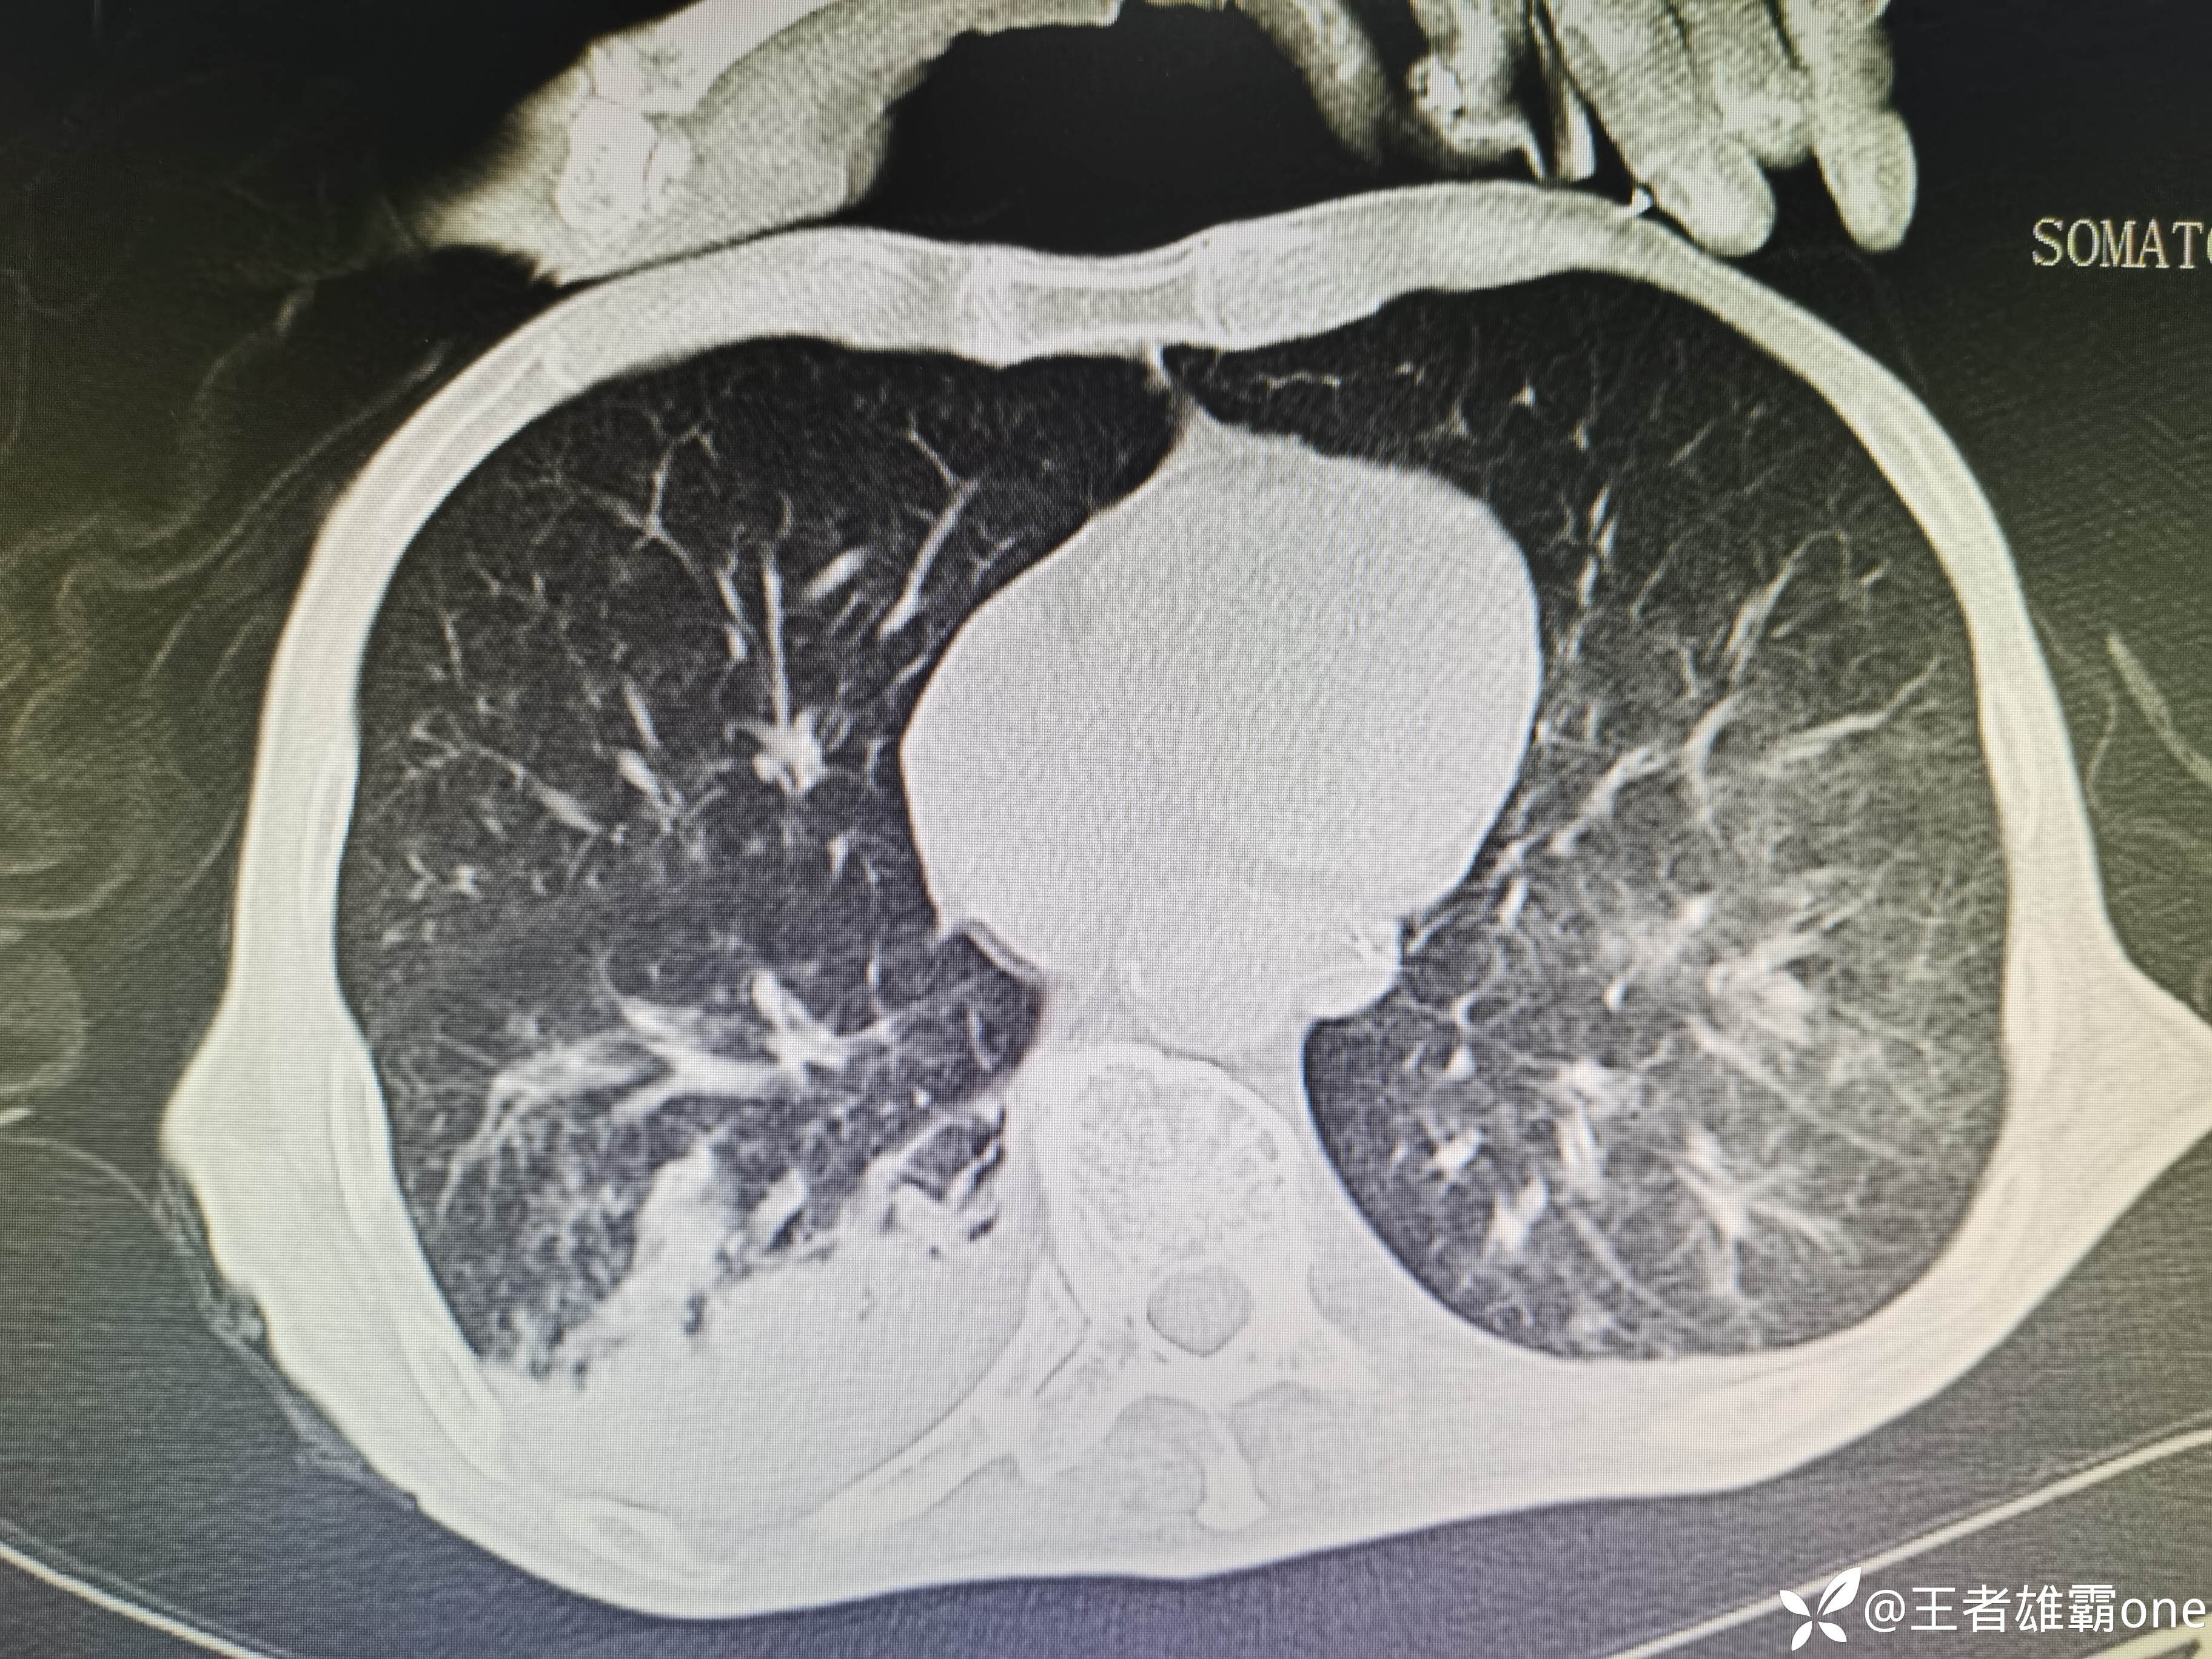

入院时胸部CT:

具体图片: